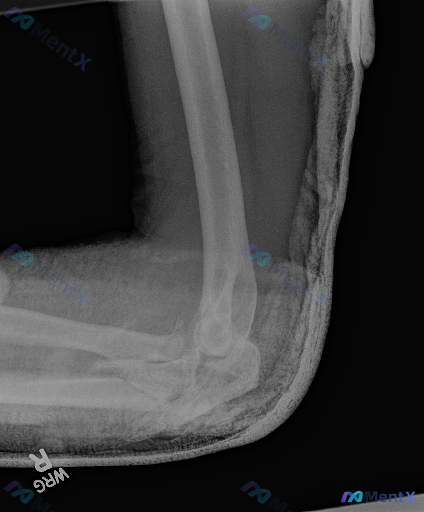

整理到一份影像分析的讨论材料,觉得挺有意思的,来问问大家的第一反应。 前提:用户明确说“这张图像存在异常”,然后给出了一张右侧肘关节侧位X光片的分析。 先放影像报告里的“阴性描述”: - 骨皮质连续,肱骨远端、桡骨头颈、尺骨鹰嘴冠突都没见明确断裂线 - 前脂肪垫征正常,后脂肪垫征阴性,关节腔好像没有...

整理了一份右肘关节的影像学病例资料,先放核心影像表现,想听听大家的第一眼思路和鉴别重点。 主要影像异常(右肘关节侧位片): 1. 尺骨近端冠突区域骨质断裂、分离 2. 桡骨头前方见游离小骨片影 3. 典型“船帆征”:前方脂肪垫扇形抬高,后方脂肪垫亦抬高 4. 肱骨与前臂骨骼对位关系异常 5. 关节周...